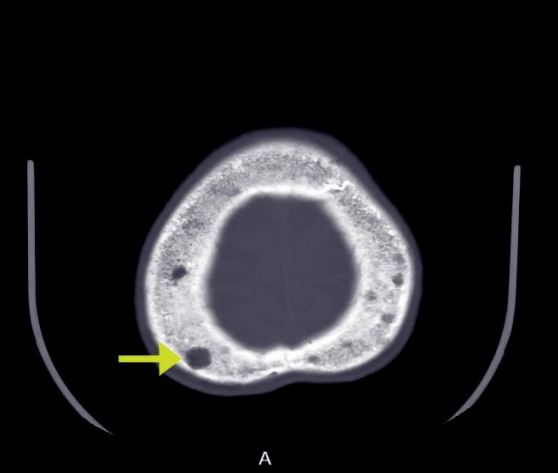

Lytic Lesions in Thal Major image

Lytic Lesions in Thal Major

Lytic Lesions in Thal Major featuring Dr. William LiPera and MaryAnn Fragola